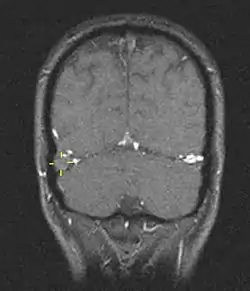

![]() خثار الجيب الوريدي المخي (الإشارات الصفراء) كما يظهر في تصوير بالرنين المغناطيسي خثار الجيب الوريدي المخي (الإشارات الصفراء) كما يظهر في تصوير بالرنين المغناطيسي | |

التصوير الطبي

تُوجد العديد من إجراءات التصوير العصبي التي تُساعد في اكتشاف خثار الجيب المخي. قد تكون الوذمة الدماغية والاحتشاء الوريدي ظاهرةً في أي طريقة تصوير، أما للكشف عن الخثرة نفسها، فإنَّ التصوير المقطعي المحوسب (CT) والتصوير بالرنين المغناطيسي (MRI) يُعتبران التقنيات الأكثر شيوعًا لذلك، حيثُ يستخدم كلاهما أنواعًا مختلفة من المواد المظللة لإجراء صورة الوريد، والتي تساعد في إظهار الأوردة حول الدماغ.[6]

يَستخدم تصوير الأوردة بالرنين المغناطيسي نفس الأُسس، ولكن التصوير بالرنين المغناطيسي يُستعمل كطريقةٍ للمسح. يمتلك التصوير بالرنين المغناطيسي ميزةً بأنهُ أفضل في اكتشاف الأضرار التي لحقت بالدماغ نفسه نتيجةً للضغط المُتزايد على الأوردة المسدودة، ولكنه غير متوافرٍ بسهولة في العديد من المُستشفيات، كما أنَّ تفسير نتائجه عادةً ما يكون صعبًا.[16]